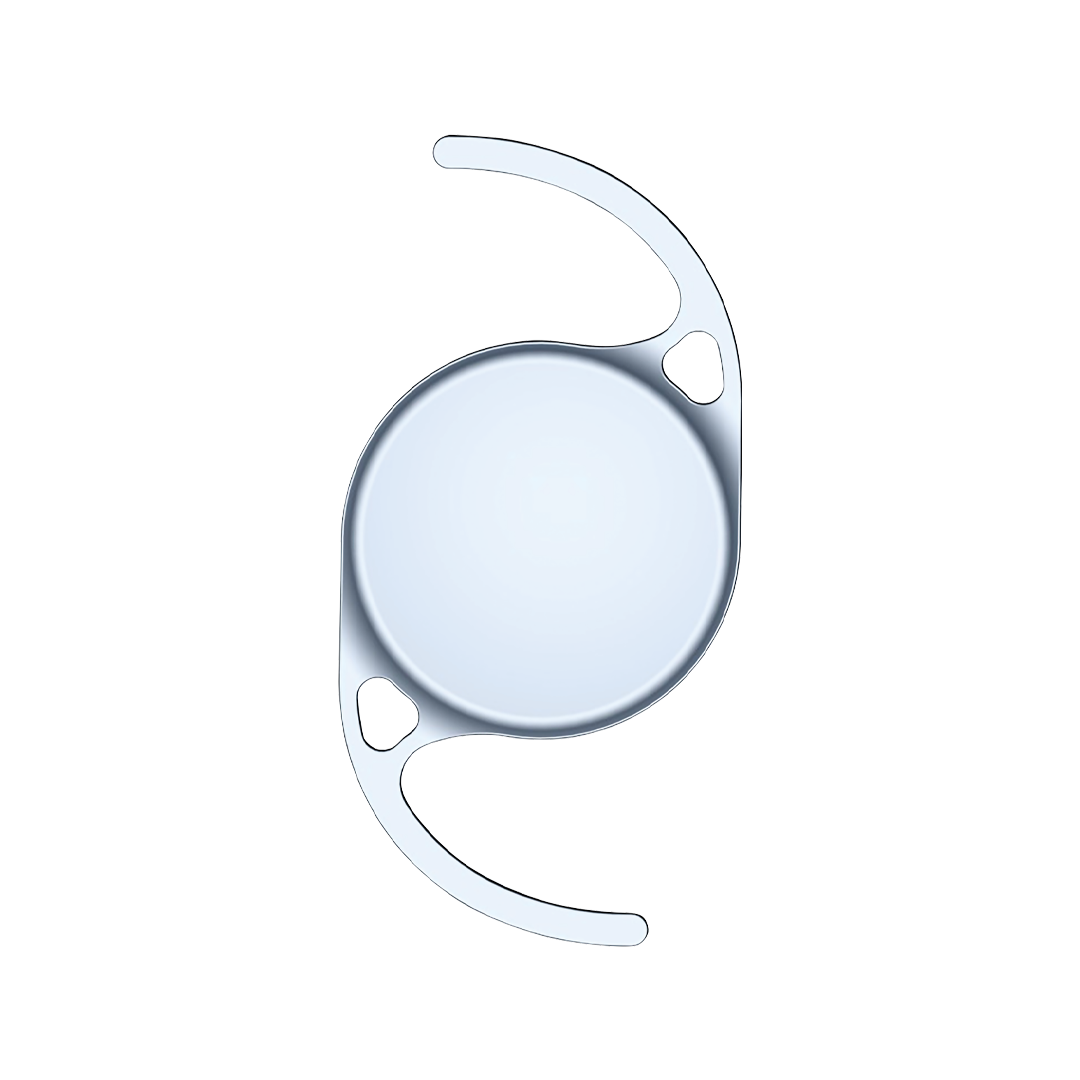

Bausch + Lomb

Intraocular Lens inVista

Intraocular Lens inVista

Monofocal intraocular lens